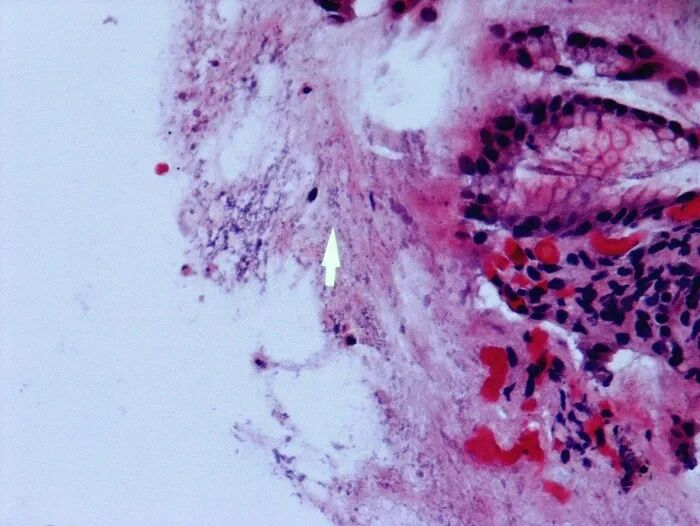

3.HP的W-S银染色法:

W-S银染色法细菌呈棕黑色或黑色,背景呈淡黄色。

图4_胃体小弯组织HP的W-S染色,HP呈杆状、黑色。细胞核黑色,对照背景黄色(40X)